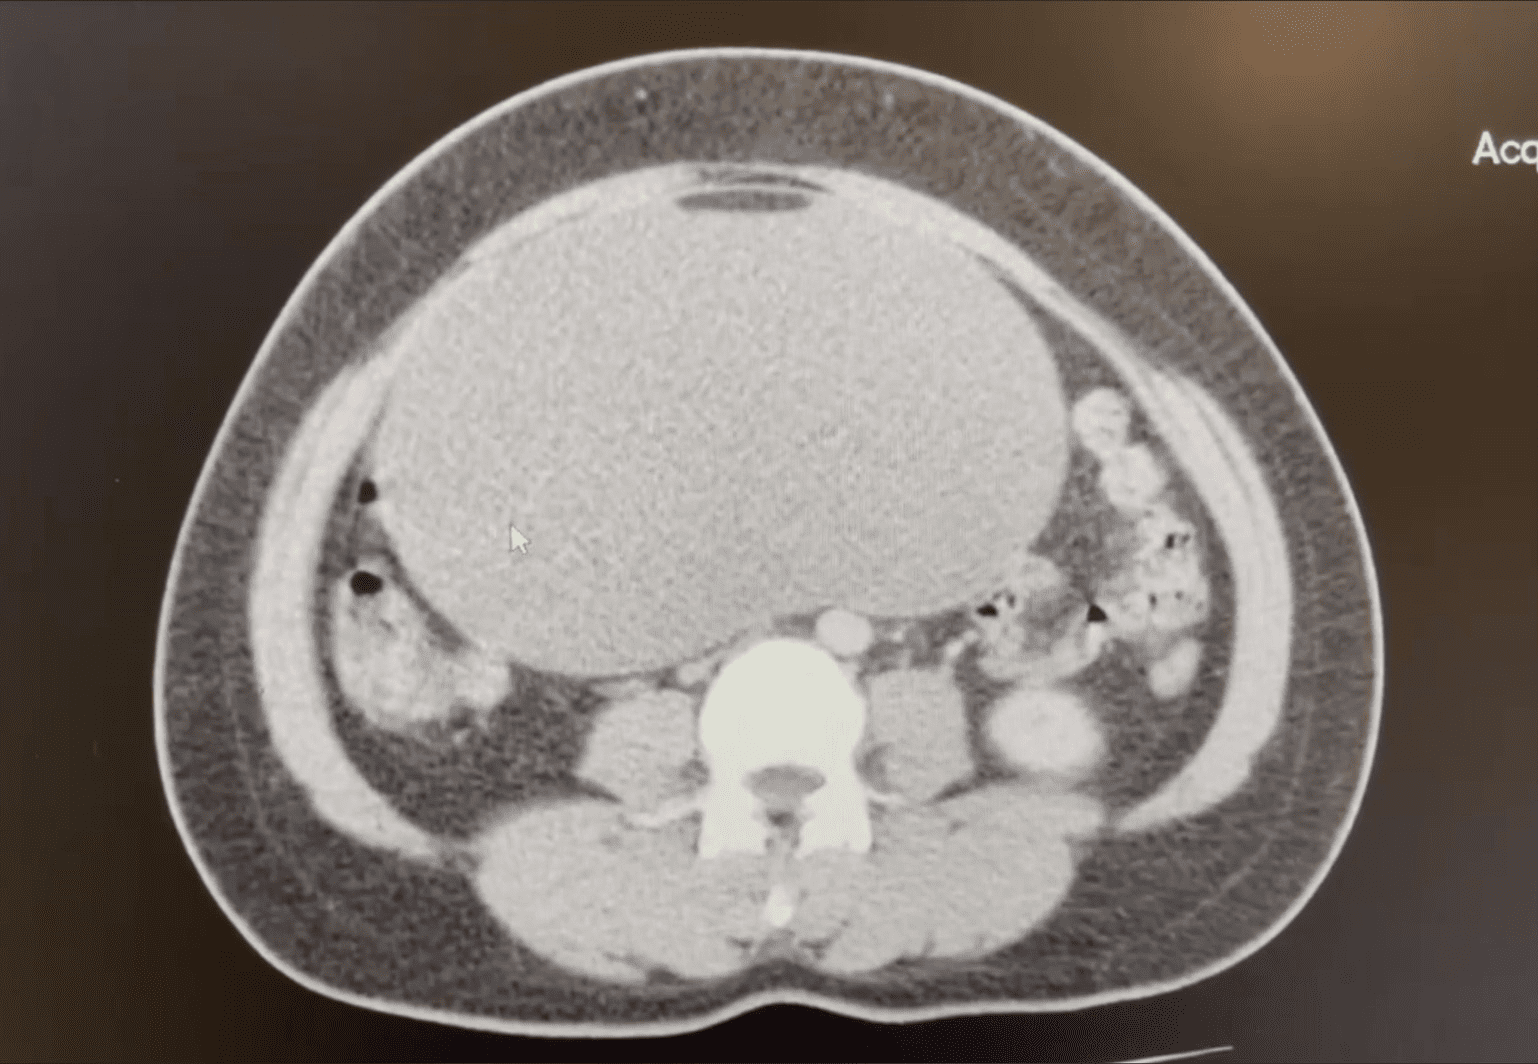

Khối u nang buồng trứng qua hình ảnh chụp cắt lớp vi tính

Bệnh nhân V.T.Tr, 34 tuổi (Bình Ngọc – Móng Cái) vào viện trong tình trạng đau bụng âm ỉ vùng quang rốn và hạ vị. Qua thăm khám và siêu âm ổ bụng, chụp cắt lớp vi tính… phát hiện phía trên tử cung có khối lớn kích thước khoảng 20x22cm, tỷ trọng đồng nhất, bên trong có ít cấu trúc mỡ và vôi hóa, bác sĩ chẩn đoán: U nang buồng trứng kích thước lớn.

Đối với khối u kích thước lớn, thực hiện mổ nội soi sẽ gặp khó khăn, đòi hỏi bác sĩ có chuyên môn cao và có kinh nghiệm. Nhận thấy khối u vẫn có thể bóc tách bằng phương pháp mổ nội soi, các bác sĩ quyết định thực hiện phẫu thuật nội soi vì đem đến cho bệnh nhân nhiều ưu điểm hơn so với mổ mở: ít xâm lấn, vết mổ nhỏ, đảm bảo tính thẩm mĩ, bệnh nhân hồi phục nhanh hơn và giảm nguy cơ biến chứng sau mổ như nhiễm trùng, dính ruột.